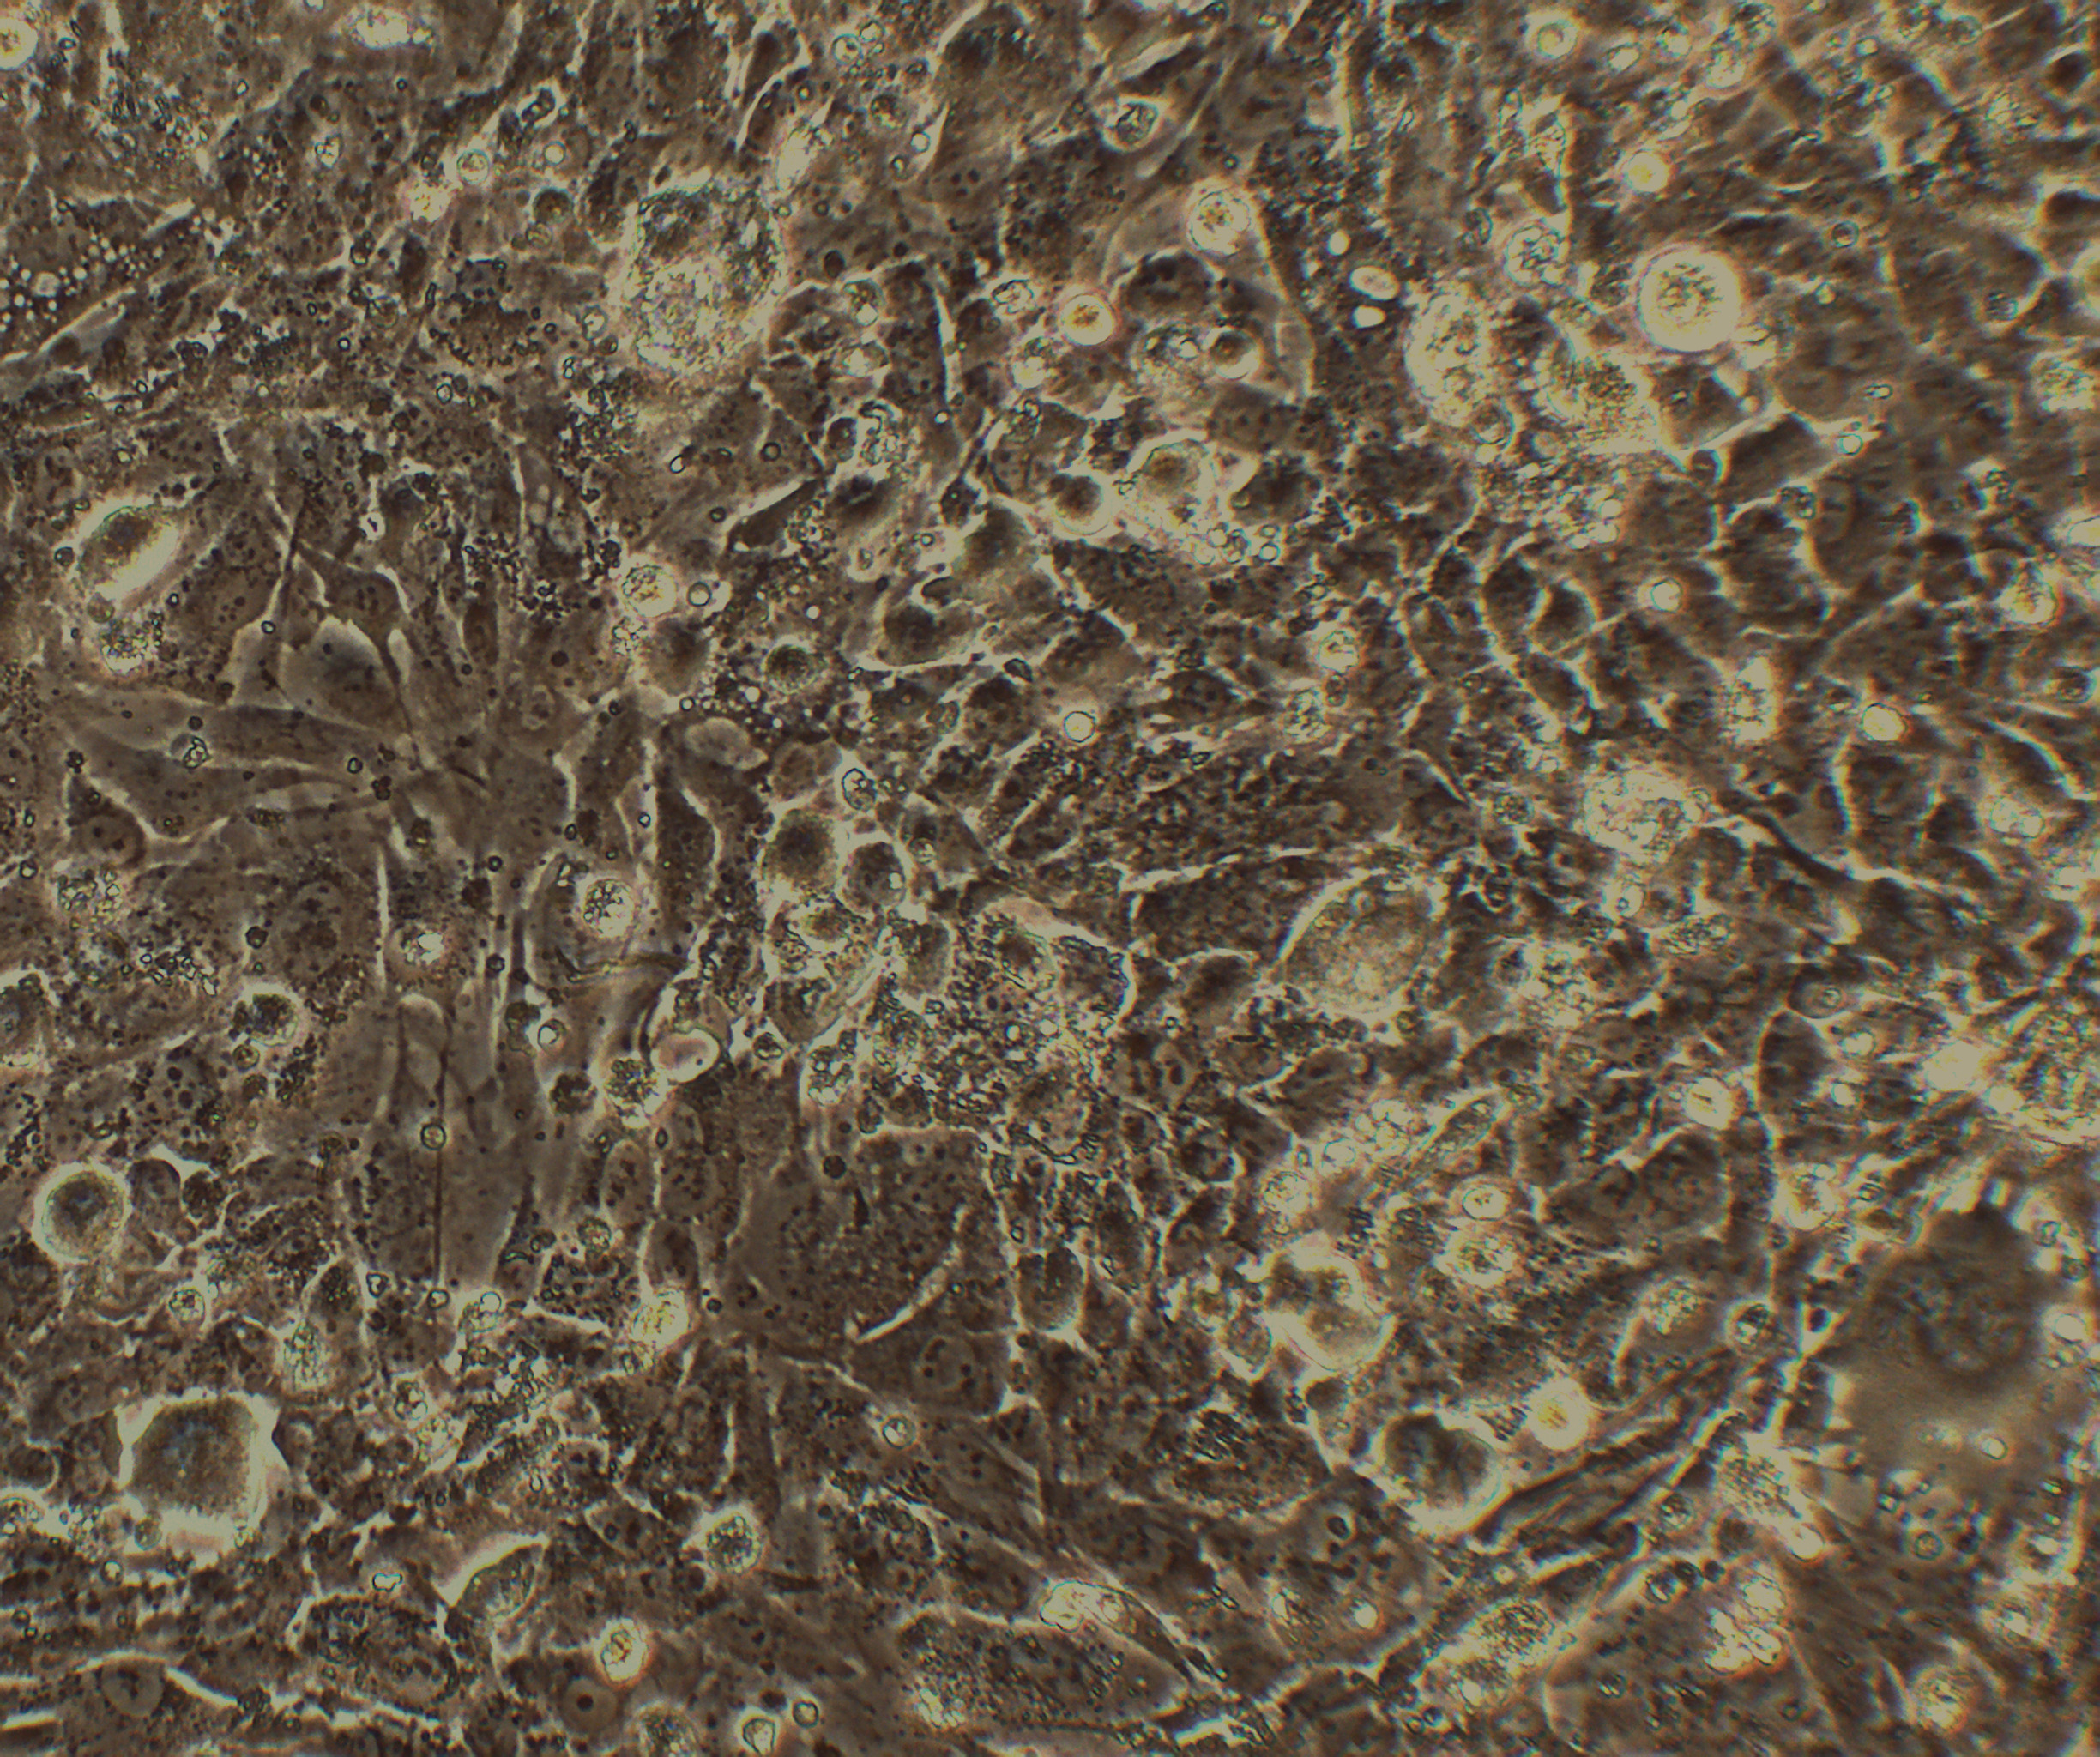

形态特征 上皮细胞样

生长特征 贴壁